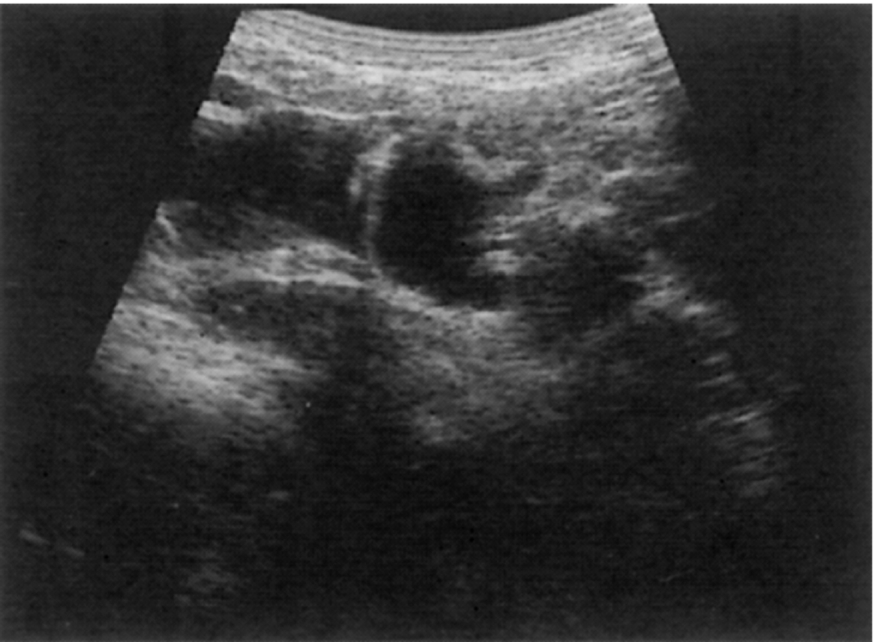

Measuring the length of the spleen is an adequate indicator of size for most purposes and provides a useful baseline for monitoring changes in disease status which is reproducible by the operator in subsequent scans and comparable to measurements obtained in cross-sectional imaging. Ultrasound is often the modality of choice in monitoring the spleen size because of lack of radiation and good operator reproducibility. A measurement of greater than 12 cm would be considered enlarged in most adults; however, as previously discussed, body size and type can impact the “normal” splenic size range. As the spleen enlarges, it extends downwards and medially. Its inferior margin becomes rounded (Figs. 5.1D–E, 5.2A), and it may extend below the left kidney and into the pelvis.

Splenic cysts have a relatively low incidence but are nevertheless the most common benign mass found in the spleen (Fig. 5.4D). Typically, cysts are rounded, with a thin wall with no internal echoes and posterior enhancement; occasionally thin septations may be seen, and also debris because of hemorrhage. Splenic cysts may occasionally be associated with autosomal dominant polycystic disease.